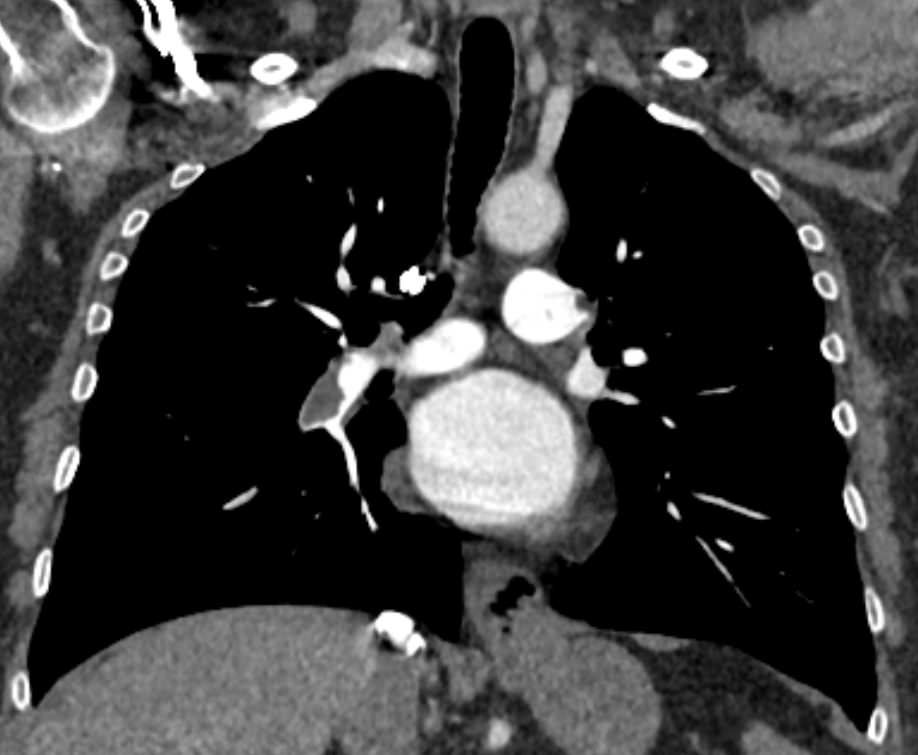

Наиболее информативным, при этом быстрым и неинвазивным (то есть без вмешательства в организм пациента), методом диагностики патологии легочной артерии является мультиспиральная компьютерная томография (КТ-ангиография). Методика основана на использовании рентгеновского излучения в сочетании с цифровой обработкой данных для получения трехмерных изображений сосудистой системы.

Для визуализации кровеносных сосудов в обязательном порядке применяется контрастное усиление. Для этого в вену пациента вводится йодсодержащий контрастный препарат, который попадая в кровоток активно поглощает рентгеновские лучи и ярко контрастирует сосудистую систему, в том числе легочной артерии, на фоне окружающих тканей. Использование контраста дает возможность визуализировать даже мелкие артерии и выявить патологию.

В наших диагностических центрах КТ-ангиография легочной артерии проводится на современных мультиспиральных компьютерных томографах экспертного уровня TOSHIBA AQUILION. Оснащение аппаратов позволяет получать детальные снимки и трехмерные изображения сосудистой системы легочной артерии, при этом применение скоростной мультисрезовой методики сканирования значительно снижает уровень лучевой нагрузки на пациента.